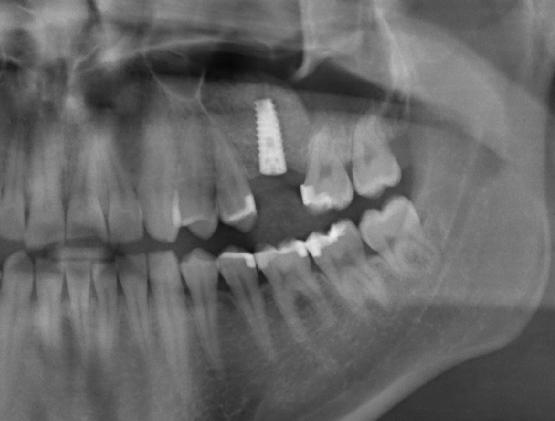

Sinus Lift With Simultaneous Implant

Sinus Lift